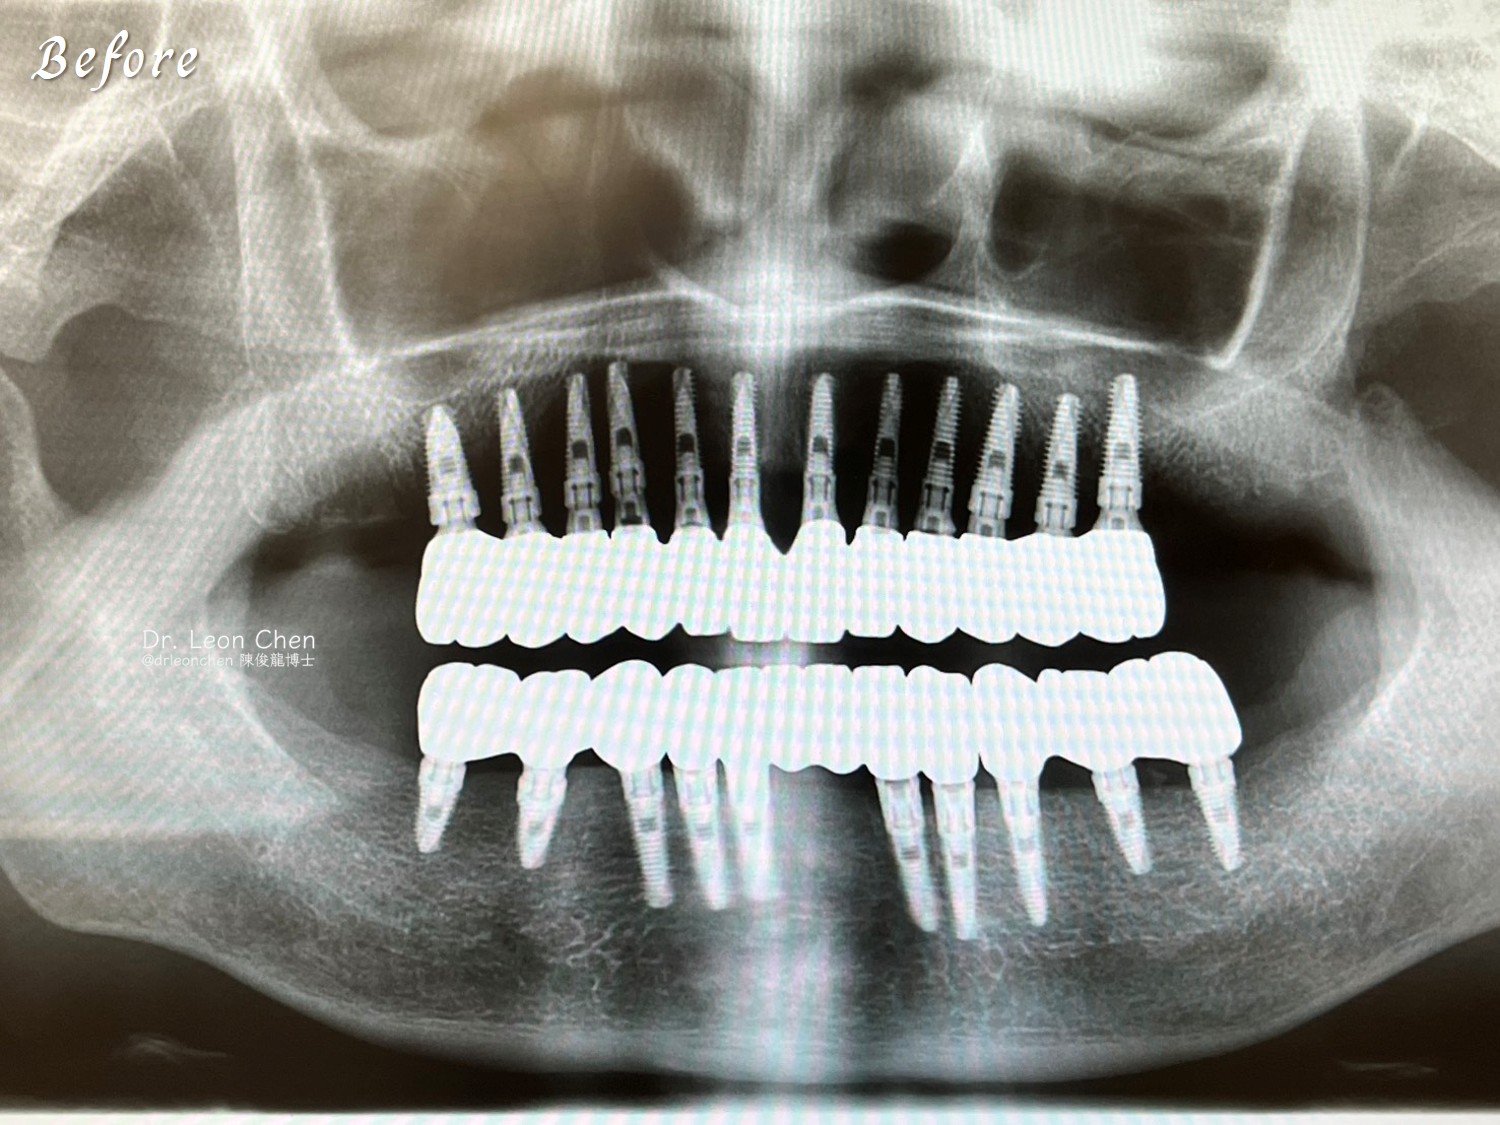

一位母親求醫無解:跨越兩年的全口重建故事

這媽媽兩年內看過20多位牙醫師,都無法解決她的問題。

她最後飛往美國找到陳醫師,用三個小時一次全口重建,把所有複雜問題一次解決。